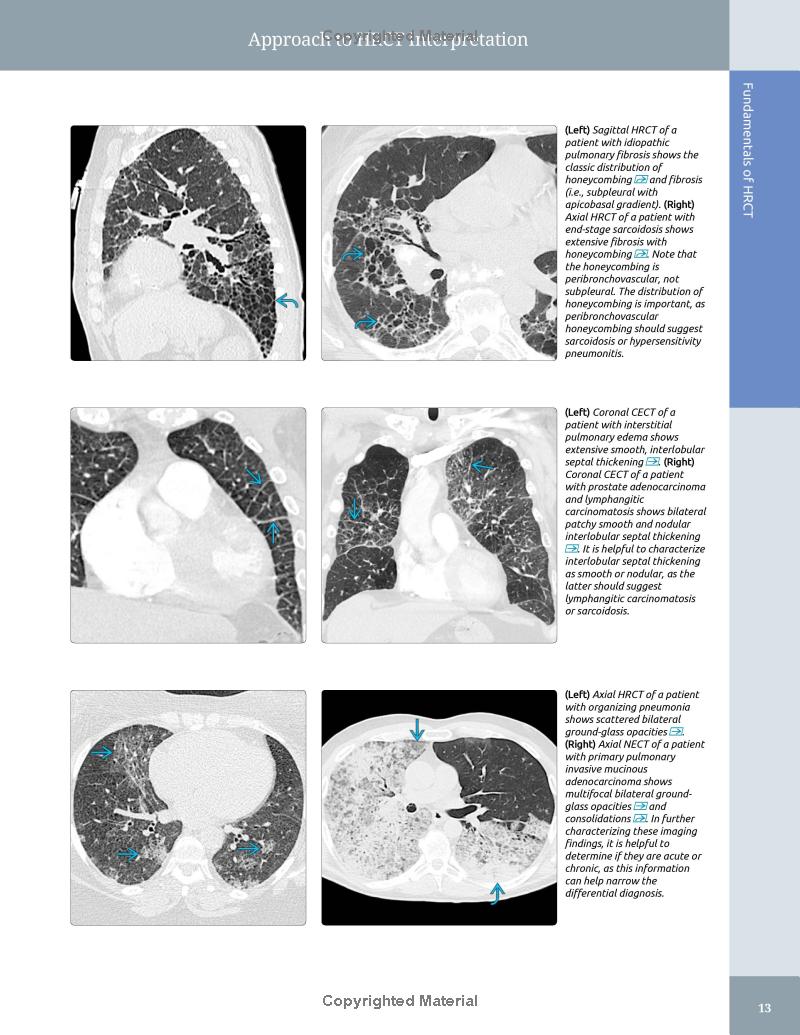

– Superb illustrations with comprehensive captions display both typical and variant findings on HRCT scans

– Introductory sections are specifically designed to lead the general radiologist to differential diagnoses from specific imaging findings, pathologic patterns, or from the disease/pathology itself